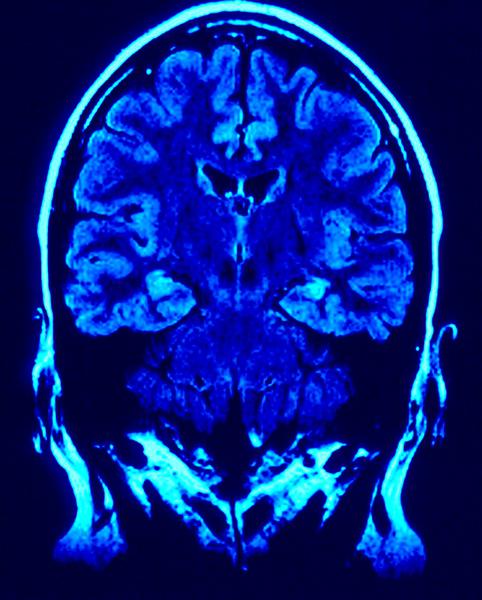

Creier, Foto: MorgueFile.com

Suntem dependenți de dragoste și din acest motiv, indiferent cât de mult sau puțin a durat o relație amoroasă, despărțirea aduce creierul într-o stare ce seamănă aceleia de la începutul relației. Tot ceea ce ne amintește de acea persoană, o fotografie, locurile în care am fost împreună, gesturi și alte lucruri aleatorii, declanșează activitatea neuronală din nucleul caudat și din mezencefal, părți ale sistemului nervos central responsabil pentru activitățile neuronale compensatorii. Aceste părți ale creierului au fost observate în experimentele de testare a activității cerebrale prin imagistică fMRI, atunci când medicii le expuneau pacienților fotografii cu persoana iubită. De asemenea, aceste părti ale creierului sunt cele care răspund și la dozarea cu nicotină și cocaină.